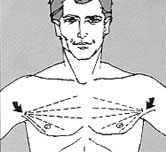

- Accumulation of fat in male breasts can produce a feminine appearance.”

- This patient’s breast contours had become rounded.

8. The diagram indicates the direction of the liposuction process taken from the small incisions (arrows) under the arms.